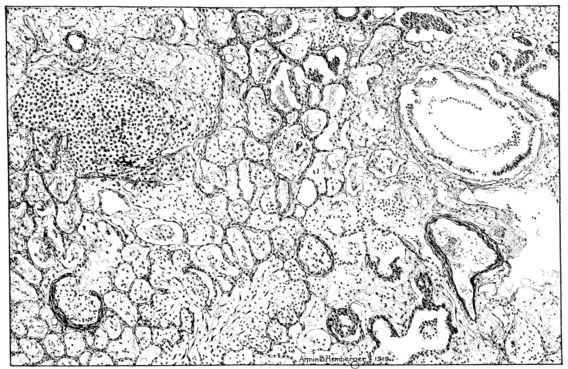

FIG. II. AUTOPSY NO. 98. DRAWING OF A SECTION THROUGH A TRACHEA SHOWING NECROTIZING HEMORRHAGIC INFLAMMATORY PROCESS OF THE MUCOSA.

FIG. III. AUTOPSY NO. 90. DRAWING FROM A LESION OF THE TRACHEA (SOMEWHAT OLDER THAN THAT ILLUSTRATED IN FIGURE II). THE MUCOSA IS ENTIRELY LACKING. CONGESTION AND EDEMA ARE THE STRIKING FEATURES IN THE SUBMUCOSA. THE NECROTIZING PROCESS HAS EXTENDED INTO THE MUCUS GLANDS. THIS IS SHOWN IN THE LOWER PICTURE.

FIG. IV. AUTOPSY NO. 205. CONGESTION AND EDEMA OF THE SUBMUCOSA AND REGENERATION OF THE TRACHEAL EPITHELIUM.

The changes are less marked, perhaps, in the trachea than in its finer ramifications. The mucosa is constantly more or less destroyed and large areas, usually focal, are entirely devoid of their epithelial covering. This is replaced by a sparse exudate, composed largely of red blood cells, mucus, a small amount of fibrin, and nuclear fragments (Fig. II). It may dip into the submucosa for a short distance, but usually these indentures are associated with the ducts of the mucous glands into which the inflammatory reaction extends. A more striking feature than the exudate, however, is the edema and the congestion of the submucosa. The loose areolar tissue of the submucosa is spread widely apart, and throughout it distended blood vessels are very conspicuous. Occasionally such a vessel is broken and actual hemorrhage appears in the submucosa. Occasionally, too, the inflammation extends down the duct to the mucous gland itself, and here, also, aplastic inflammatory reaction is evident, inasmuch as the acini now stain intensely red with the cells undifferentiated from each other and specked here and there by broken remains of the dead nuclei (Fig. III). After the disease has continued for a short period, even at the end of five or six days, some regeneration of the epithelial lining may be seen (3) (Fig. IV). But despite this, the acute picture persists, and there goes on, side by side, an attempted repair characterized by epithelial regeneration and the same evidence of acute change. Since the lesion is essentially a superficial one, scars or contractures of any extent are not encountered in the trachea, even in examples of the disease that have ended fatally only after many weeks.[4]